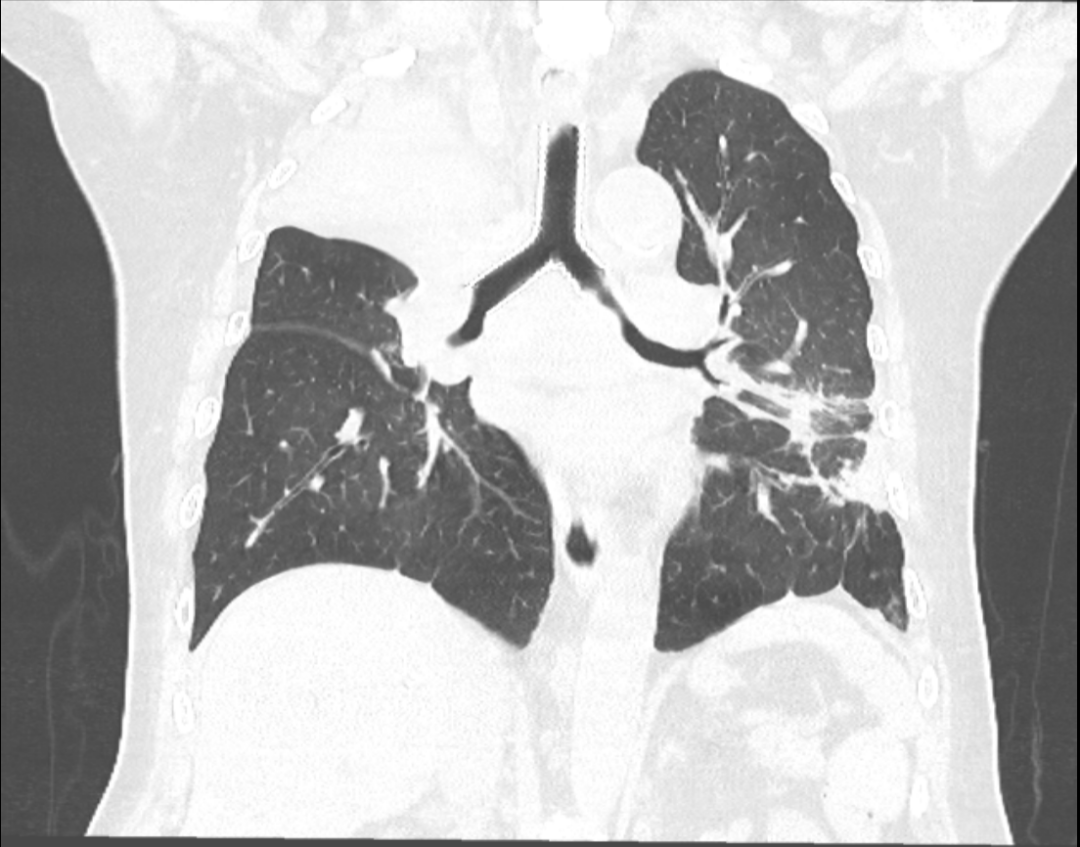

患者2同样是一位老年男性,因突发性气短3天来常营院区就诊。急诊胸部CT显示主气管下段及左主支气管起始部存在重度狭窄。王峰主任迅速决定将患者转入常营院区呼吸介入病房。在对患者进行初步气管镜检查后,发现气管III区有新生肿物,几乎完全堵塞了主气管,患者随时面临窒息死亡的风险,危在旦夕。王峰主任立即在镜下进行激光减瘤治疗,部分消除了侵入气管内的肿物,并同时置入直筒支架,以进行气管恶性狭窄的临时治疗。患者的生命暂时得到保障,但后续治疗仍面临诸多挑战。几天后,气管镜下肿物的病理结果确认为鳞状细胞癌。为了进一步确保患者气道的通畅,并为后续的全身治疗争取时间,经过呼吸介入与麻醉团队的精心评估和围术期评估后,王峰带领团队成功为患者置入“Y型气管覆膜支架”,该支架同时支撑起了气管中下段及左主支气管起始部的狭窄部分。患者的呼吸困难等症状得到明显缓解。

患者术前CT